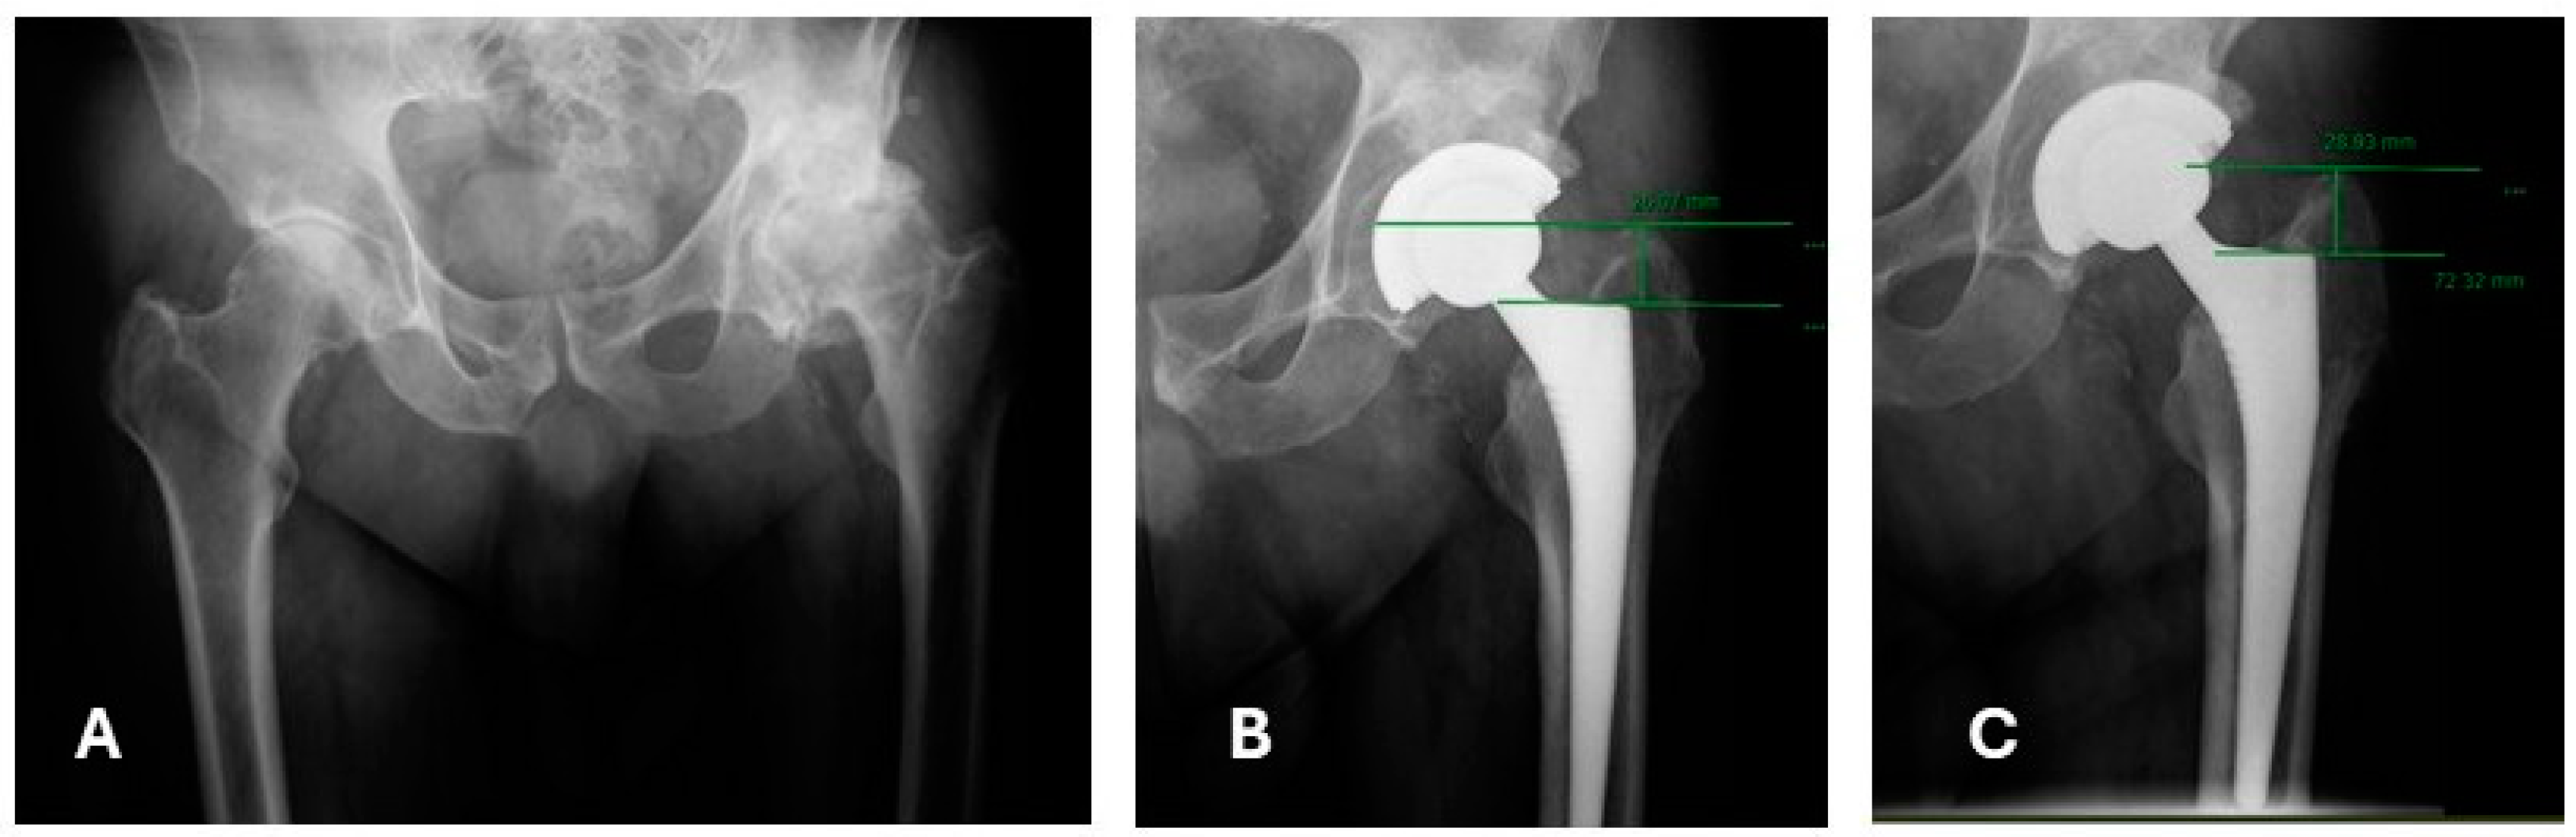

2.4. Postoperative Radiographic Assessment